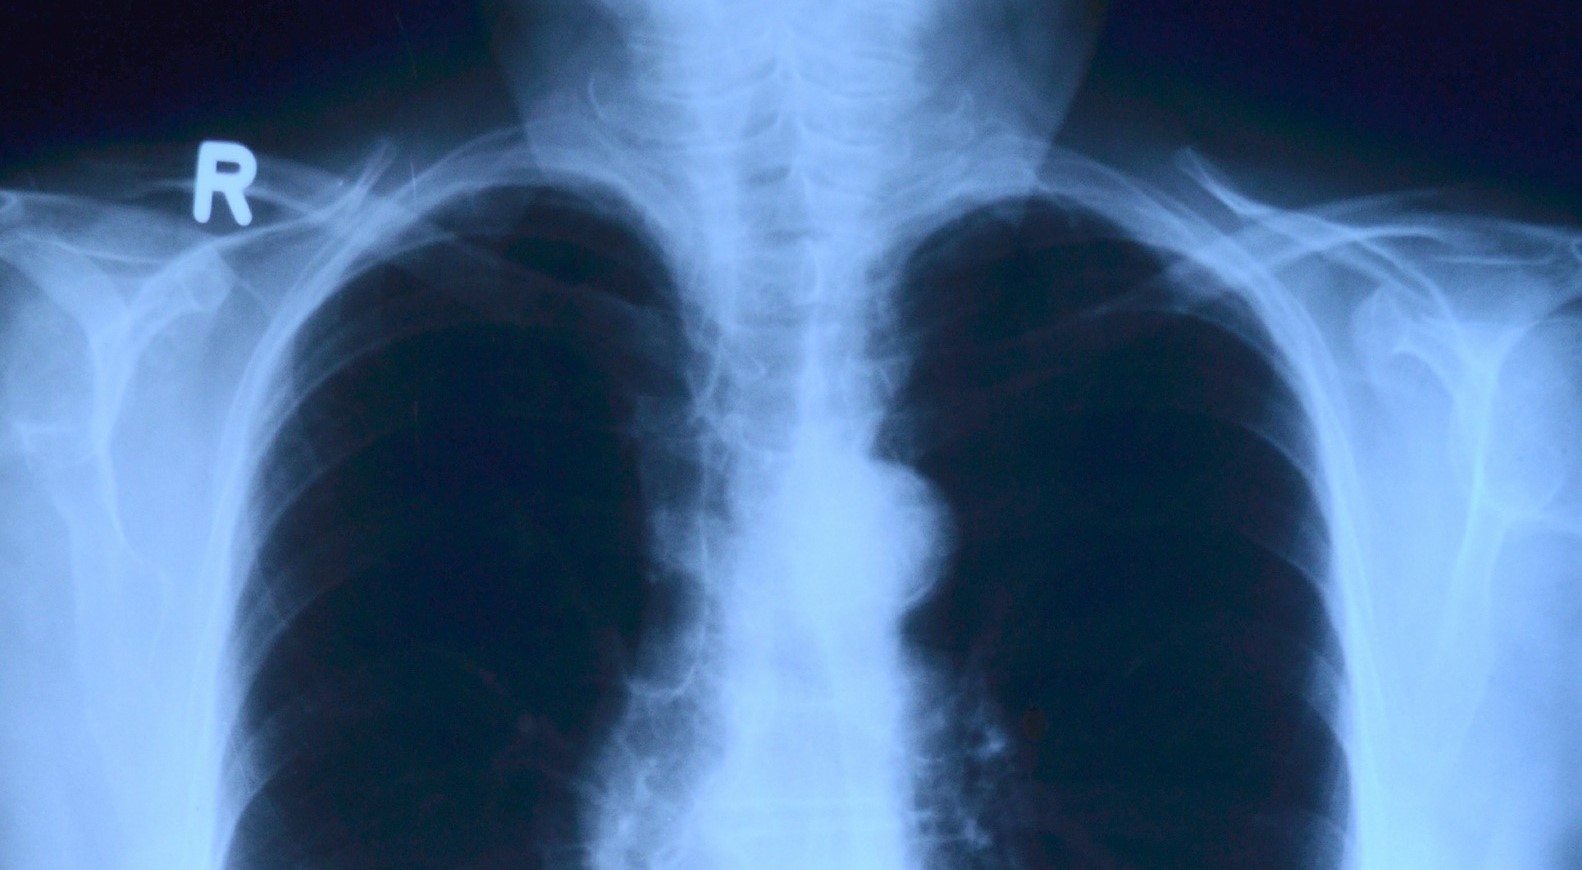

Тольяттинские врачи рассказали, как защитить себя и детей от туберкулеза

Медики поясняют, что основной источник заражения - человек, который сам болеет туберкулезом легких. Когда зараженный кашляет, выделяется мокрота , где и содержатся опасные бактерии. Коварство этой инфекции в том, что мокрота оседает на поверхности пола, земли, предметах, вещах. А это значит, что нарушение гигиены может привести к заражению туберкулезом и без прямого контакта с зараженным. Поэтому особое внимание нужно уделять дезинфекции рук после посещения общественных мест, мыть овощи и фрукты, хорошо обрабатывать мясо и молоко.